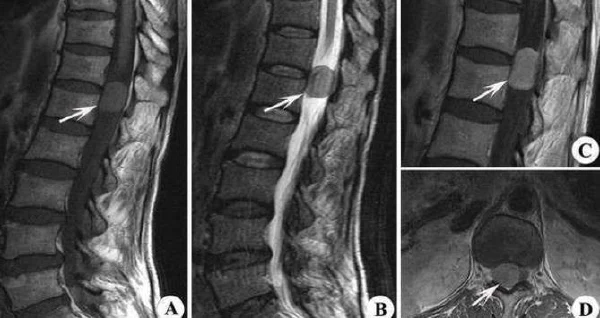

腰椎肿瘤是指位于脊椎和脊髓周围的肿瘤。根据其性质,可以分为良性和恶性,且可能会压迫脊髓、神经根或脊椎,导致各种神经功能障碍。大多数腰椎肿瘤的病因尚不完全明确,但可能与遗传因素、免疫功能异常或辐射暴露等有关。

腰椎肿瘤的症状可能因肿瘤的大小、位置及生长速度等因素而异,但常见的症状包括局部疼痛、神经根痛、下肢无力、感觉异常及大小便功能障碍。疼痛是最常见的初始症状,通常呈持续性且难以缓解,夜间尤其明显。

据相关研究,腰椎肿瘤的疼痛主要是由于肿瘤的机械压迫和炎症反应引起的[1]。此外,肿瘤生长过程中产生的生物活性物质也可能导致局部组织的炎症和疼痛。如果不及时治疗,腰椎肿瘤可能对神经系统造成不可逆的损伤,导致严重的神经功能障碍和生活质量下降。